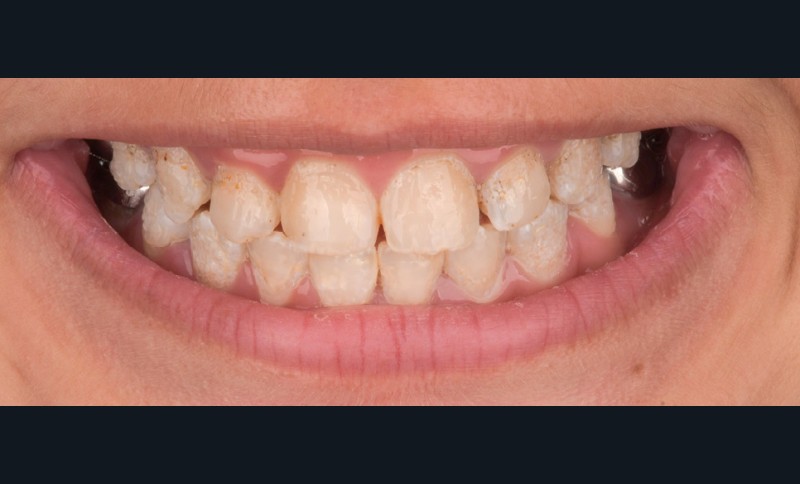

Lors de l’arrivée de la patiente, un examen clinique au fauteuil est effectué, complété par une empreinte numérique permettant l’enregistrement précis des arcades dentaires et de l’occlusion existante. Cet examen initial met en évidence une pathologie de type amélogenèse imparfaite. On note également la présence de couronnes métalliques au niveau des premières molaires, ainsi que de multiples restaurations, notamment au niveau des dernières molaires (fig. 1 à 4).

La première étape décisionnelle repose sur une analyse esthétique du visage et du sourire, réalisée à l’aide du logiciel SmileCloud. Cette analyse permet d’évaluer les proportions dentaires, la ligne du sourire et les rapports dento-labiaux. Elle confirme que le traitement vise à la fois la protection d’un émail de mauvaise qualité et l’amélioration de l’esthétique globale, avec notamment une optimisation des proportions dentaires (fig. 5 et 6).